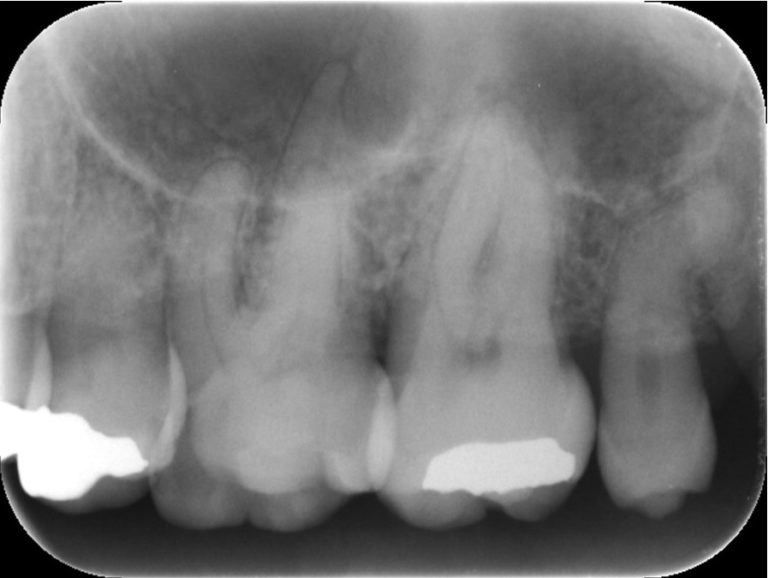

なので抜歯の際はもっと限局的に診断するためにデンタルX線写真も撮影します。

こうして初めて、「あれ、この親知らずは意外と手強いかもな」と考えるのです。

一見、小臼歯のような小さな親知らずで、簡単に抜けそうですが、根っこの形態を確認すると、遠心方向にかなり曲がっていました。

こういった場合、慎重に力を加えないと根尖が折れてしまって面倒なことになる場合があります。

ゆっくりと力を加え慎重に抜歯を行い、無事に折れることなく抜歯できました。

レントゲン通り、だいぶ曲がった親知らずでした。